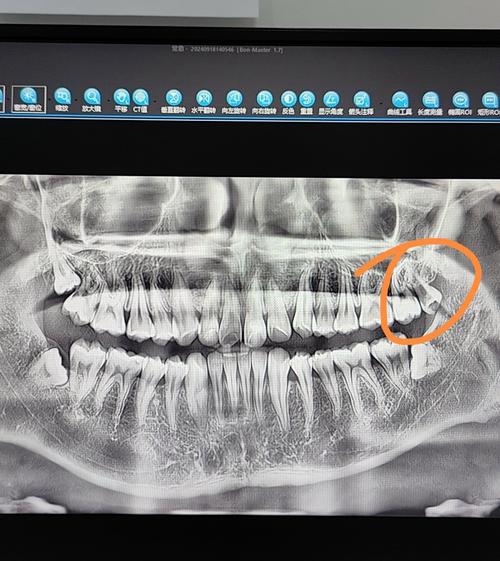

- 术前检查:通过口腔全景片(曲面断层片)或CBCT(锥形束CT)判断智齿位置、萌出方向、与邻牙及下牙槽神经的关系,评估手术难度,若存在急性炎症,需先抗炎治疗,待炎症控制后再拔除。

- 术前评估:通过口腔检查、CBCT测量牙槽骨骨量,评估骨质类型(Ⅰ-Ⅳ类),判断是否需要植骨(如骨量不足,可植入骨粉、骨膜引导骨再生)。